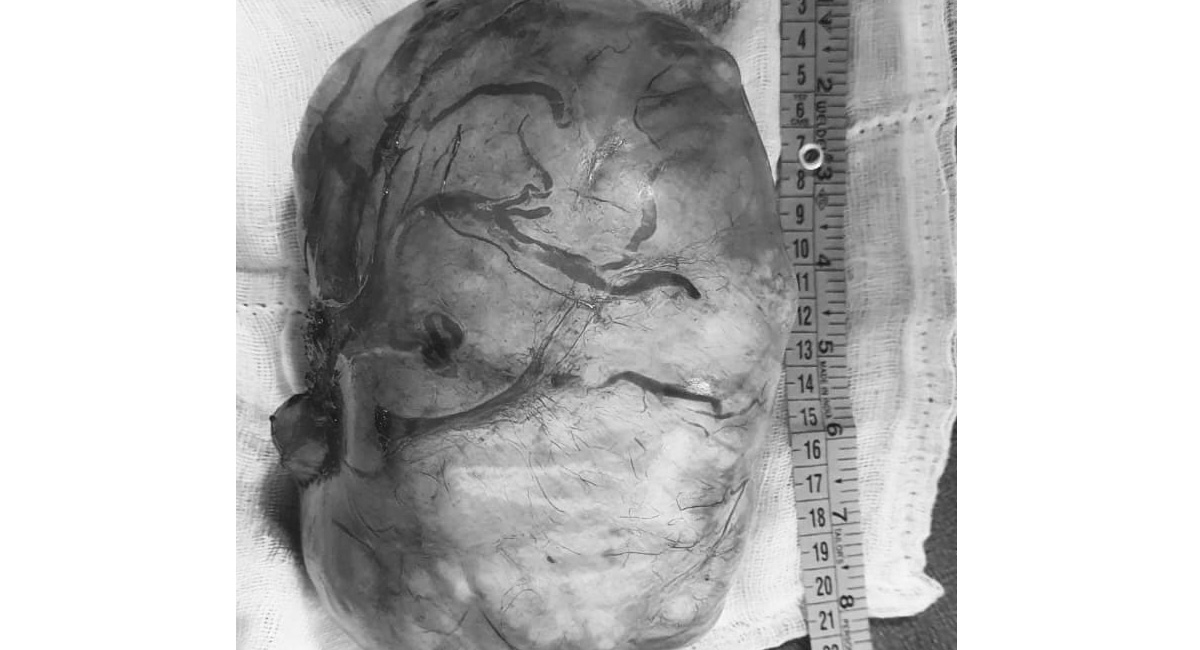

Hyderabad: Surgeons at SLG Hospitals, Nizampet on Friday announced that they have surgically removed a giant fibroid weighing 3 kg, which was equivalent of a full-term baby in size, to save the life of a 30-year-old woman.

The woman, who recently returned to India from the US, was admitted to SLG Hospitals on April 18 with severe abdominal pain. Tests revealed presence of a large fibroid in the uterus, which was causing severe abdominal pain, compression of urinary bladder, ureters, intestines, and diaphragm, impacting her lung capacity.

Dr. Shilpa Gatta, Gynaecologist and Laparoscopic Surgeon, SLG Hospitals said, “Three years ago, the patient underwent C-section in the US, but the fibroid was not detected then. Due to large size it was extremely vascular and the surgery took more than three hours and was performed with a lot of precision to prevent bleeding.”

Post-surgery, the patient recovered under critical care team led by Dr. Suhasini. Gynaecologist and Laparoscopic Surgeons, Dr Shilpa Gatta, Dr. Sirisha Mullamuri, Urologist Dr. Sivaraj Manoharan, Anaesthesiologists Dr. Srinivas,Dr. Tejashree and Dr Siri Bhavani conducted the surgery.